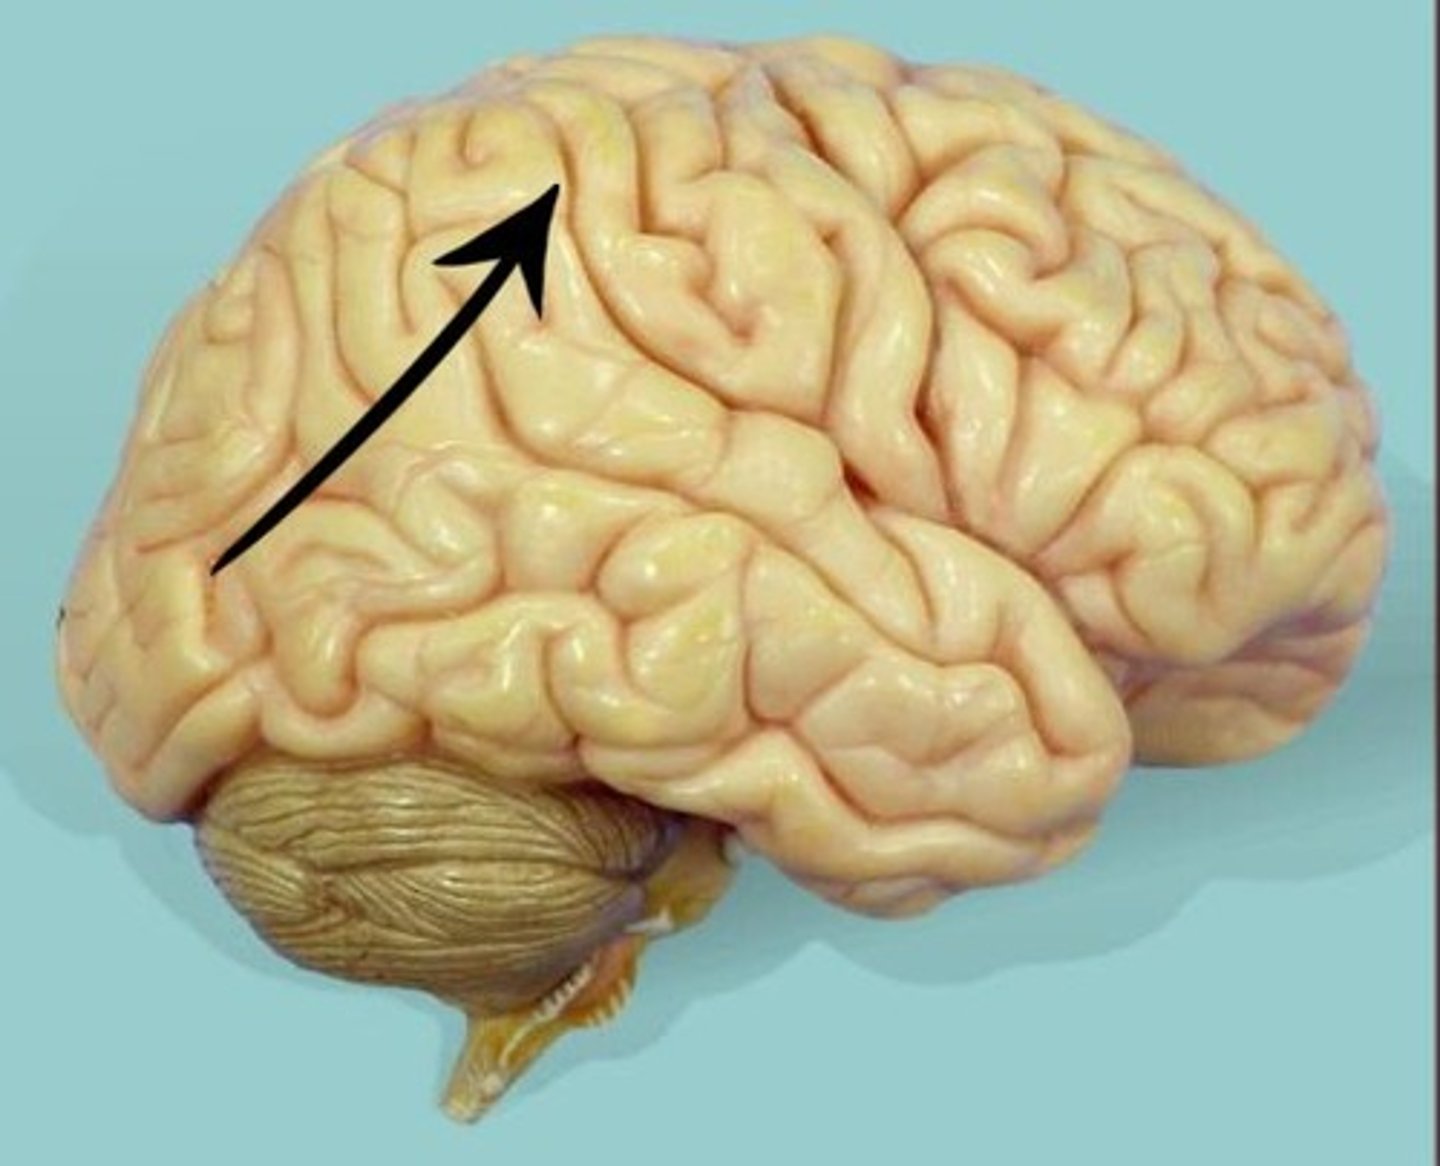

frontal lobe